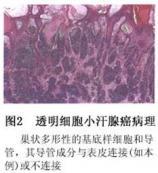

汗腺癌

628健康網(wǎng)為您分享有關(guān)汗腺癌的癥狀,汗腺癌的治療方法,汗腺癌的預(yù)防知識(shí),汗腺癌的癥狀圖片,汗腺癌吃什么藥,汗腺癌怎么治...